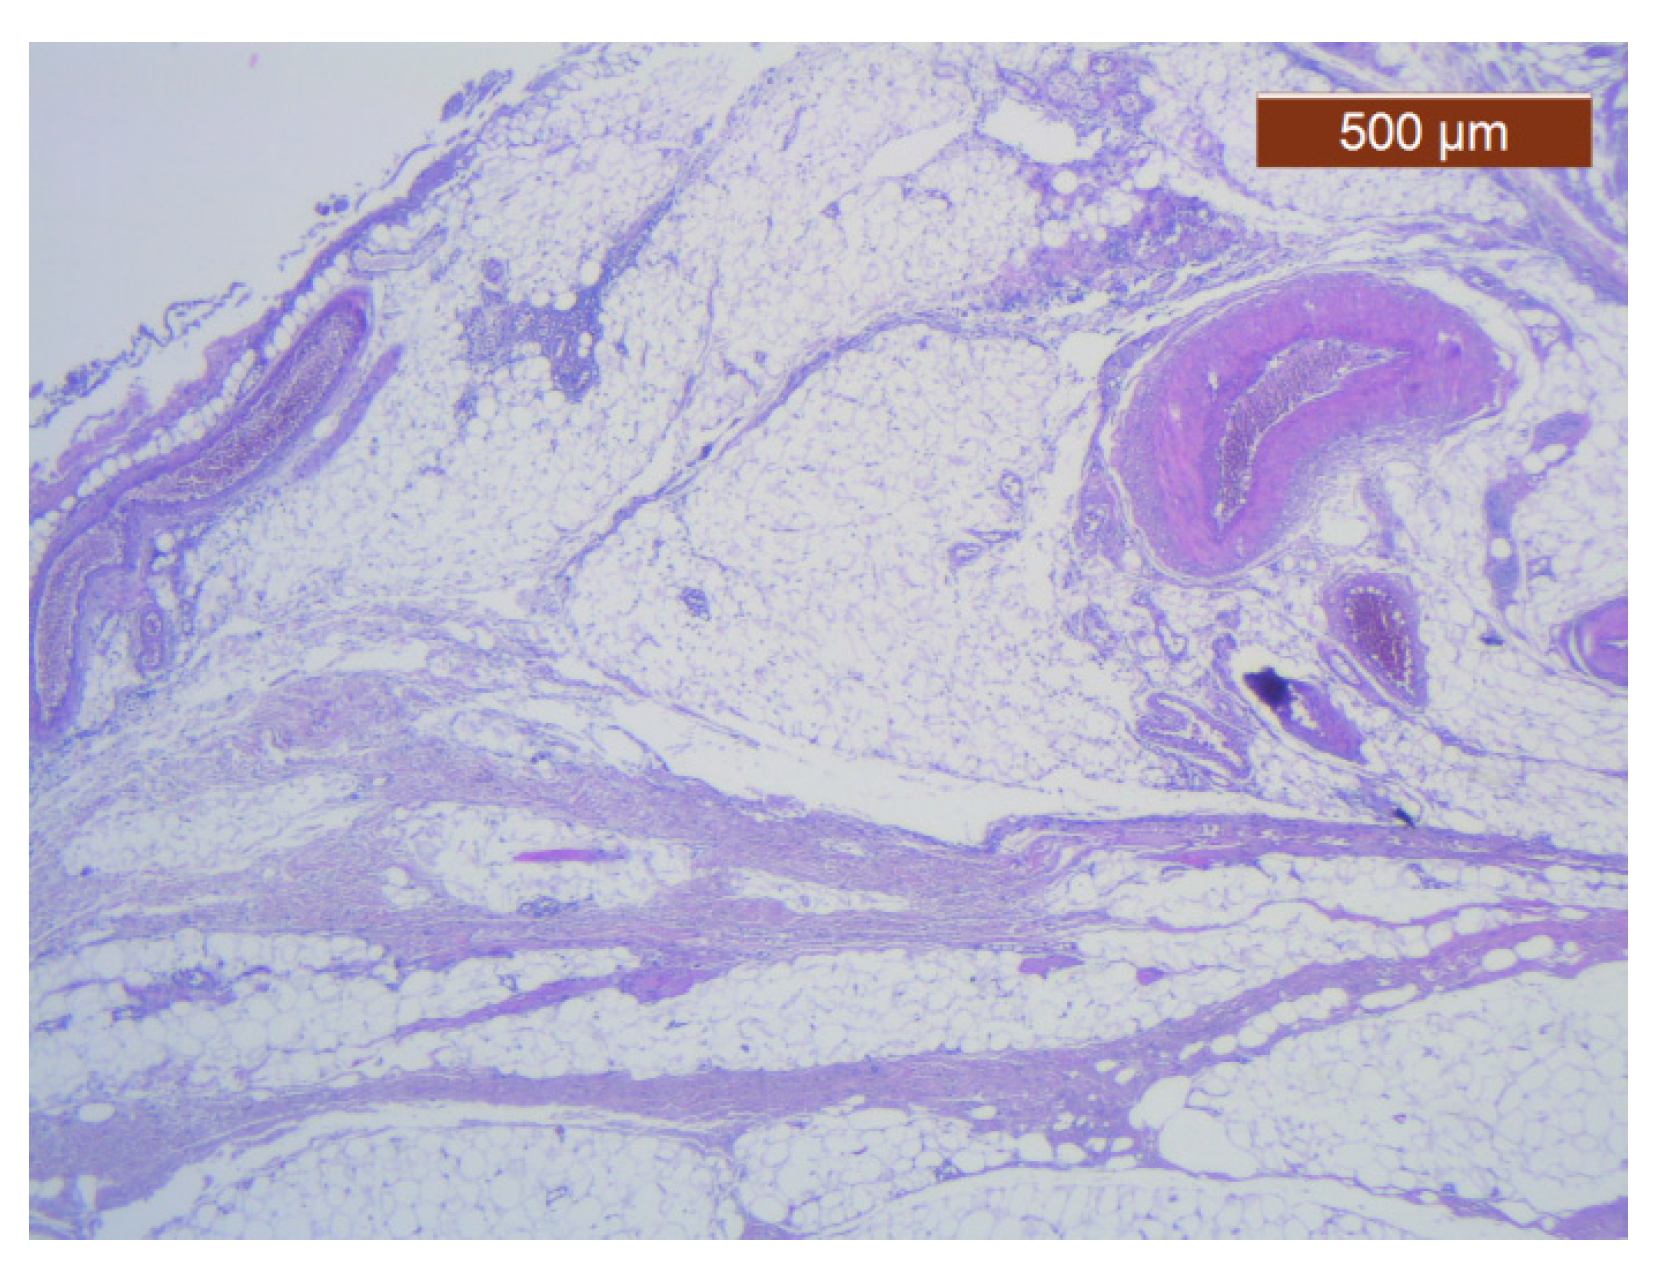

We have grouped the study results according to the topography of the anatomical specimens collected. During the study of the resection pieces, we applied the HE and IHC techniques.

Through the usual staining, a very well-represented layer of collagen can be observed at the levels of both lips (Figure 23 and Figure 24).

Muscle fibers are also visible and take direct cutaneous insertion, perpendicular to the skin, crossing the superficial fascia (Figure 25 and Figure 26).

At the labial level, the usual stains could only identify the blood vessels with a caliber of more than 1 mm, which serve the muscle groups and the submucosal glands (Figure 27).

Figure 23. Fibroadipose tissue over the SMAS, well represented with the average thickness of the soft tissue structure (HE ×2.5). Histological piece from biopsy of the lower lip.

Figure 24. General histological view that showed the depth of the SMAS from the surface of the skin (HE ×2.5). Histological piece from biopsy of the lower lip.